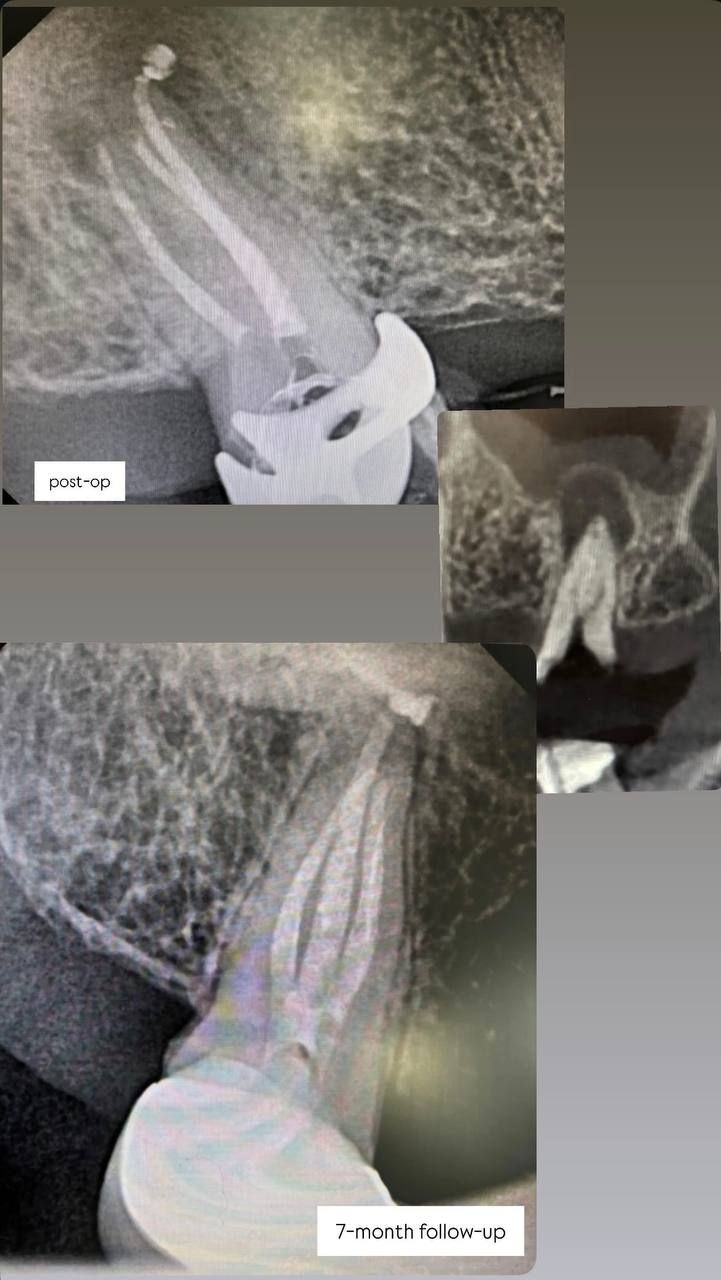

Jestem lekarzem dentystą zajmującym się stomatologią zachowawczą oraz leczeniem kanałowym pod mikroskopem (endodoncja mikroskopowa). W swojej pracy stawiam na kompleksowe podejście do zdrowia jamy ustnej – dokładną diagnostykę, skuteczne leczenie oraz profilaktykę.

Specjalizuję się w leczeniu próchnicy, odbudowie zębów oraz leczeniu kanałowym, w tym leczeniu kanałowym pod mikroskopem, które pozwala na bardzo precyzyjne oczyszczenie i opracowanie kanałów korzeniowych. Dzięki zastosowaniu mikroskopu możliwe jest skuteczne leczenie nawet bardziej skomplikowanych przypadków oraz powtórne leczenie kanałowe (reendo).